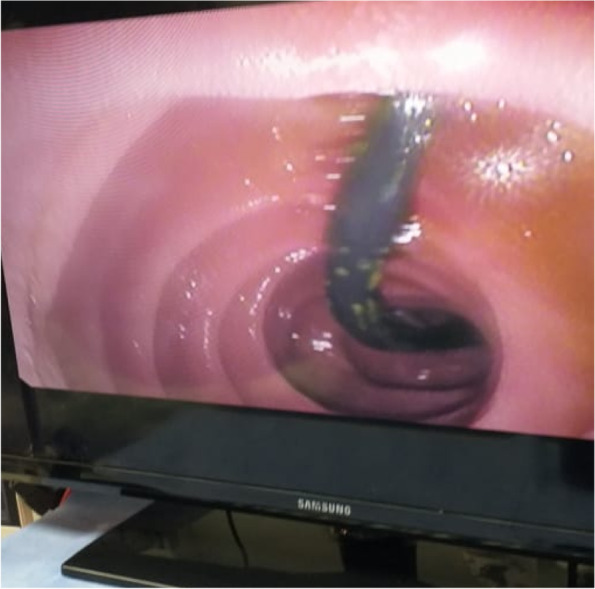

The CBD was cannulated after strenuous extraction of a long (20 cm) catheter that was largely displaced into the duodenal lumen. Cholangiogram revealed mildly dilated CBD with multiple large stones accompanied by mildly dilated central biliary radicals. Surprisingly, an old stent was hardly seen inside the dilated CBD, with mild dilatation of the intrahepatic biliary channels (Figs. 4, 5, and 6).

Papillotomy and papilloplasty were undertaken followed by stones’ extraction by a balloon extractor. The procedure was ended by inserting 2 plastic stents (10 cm× 10 f), and a flow of thick dark bile was inspected.